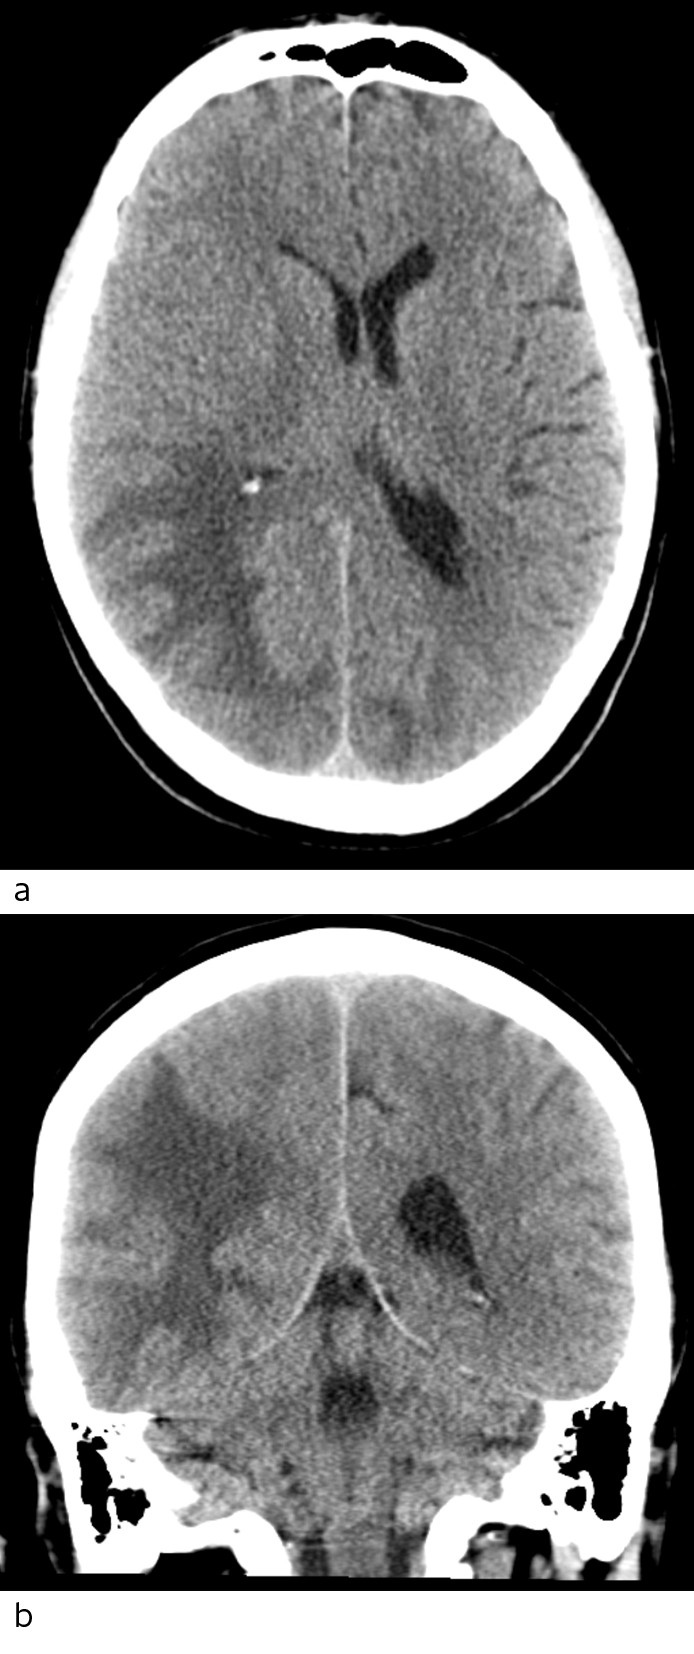

The MRI with intravenous contrast (Fig. 2) showed increased signal in the white matter in the right temporal and occipital regions, and in the medial left occipital region on T2 weighted and FLAIR sequences. There was no restriction on a diffusion-weighted series (as usually seen in stroke, abscess and tumours), but an increased apparent diffusion coefficient (ADC), consistent with vasogenic oedema. There was no pathological contrast enhancement or contrast-enhanced lesions, which would point to metastases, abscess or primary brain tumour, but numerous punctate haemorrhages were seen in the cortex of the corresponding areas on susceptibility-weighted sequence. MRI spectroscopy showed normal metabolite distribution, which also weighed against tumour.

Figure 2 Head MRI. a) ADC map with high values consistent with vasogenic oedema. b) Susceptibility-weighted imaging (SWI)…

Figure 2 Head MRI. a) ADC map with high values consistent with vasogenic oedema. b) Susceptibility-weighted imaging (SWI) shows numerous punctate lesions with a very low signal, consistent with microhaemorrhages spread through the cortex of both hemispheres, predominantly in the right occipital lobe.